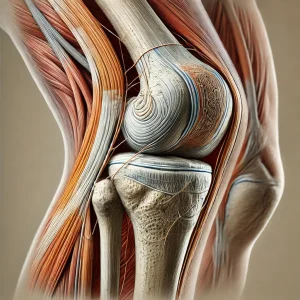

En su correcto funcionamiento están implicados los principales Huesos de la articulación Fémur, Tibia, Rótula y Peroné, los Ligamentos Colaterales y Cruzados , que confieren la estabilidad de la articulación, los Meniscos interno y externo, estructuras fundamentales de fibrocartílago cuya función como amortiguadores de impactos y como ayuda para prevenir el desgaste del Cartílago Articular, que recubre los huesos de la articulación y evita el desgaste progresivo es fundamental.

Los principales Músculos y Tendones que se insertan en la rodilla trabajan de forma coordinada y equilibrada para conseguir su correcto movimiento y evitar el deterioro de la articulación.